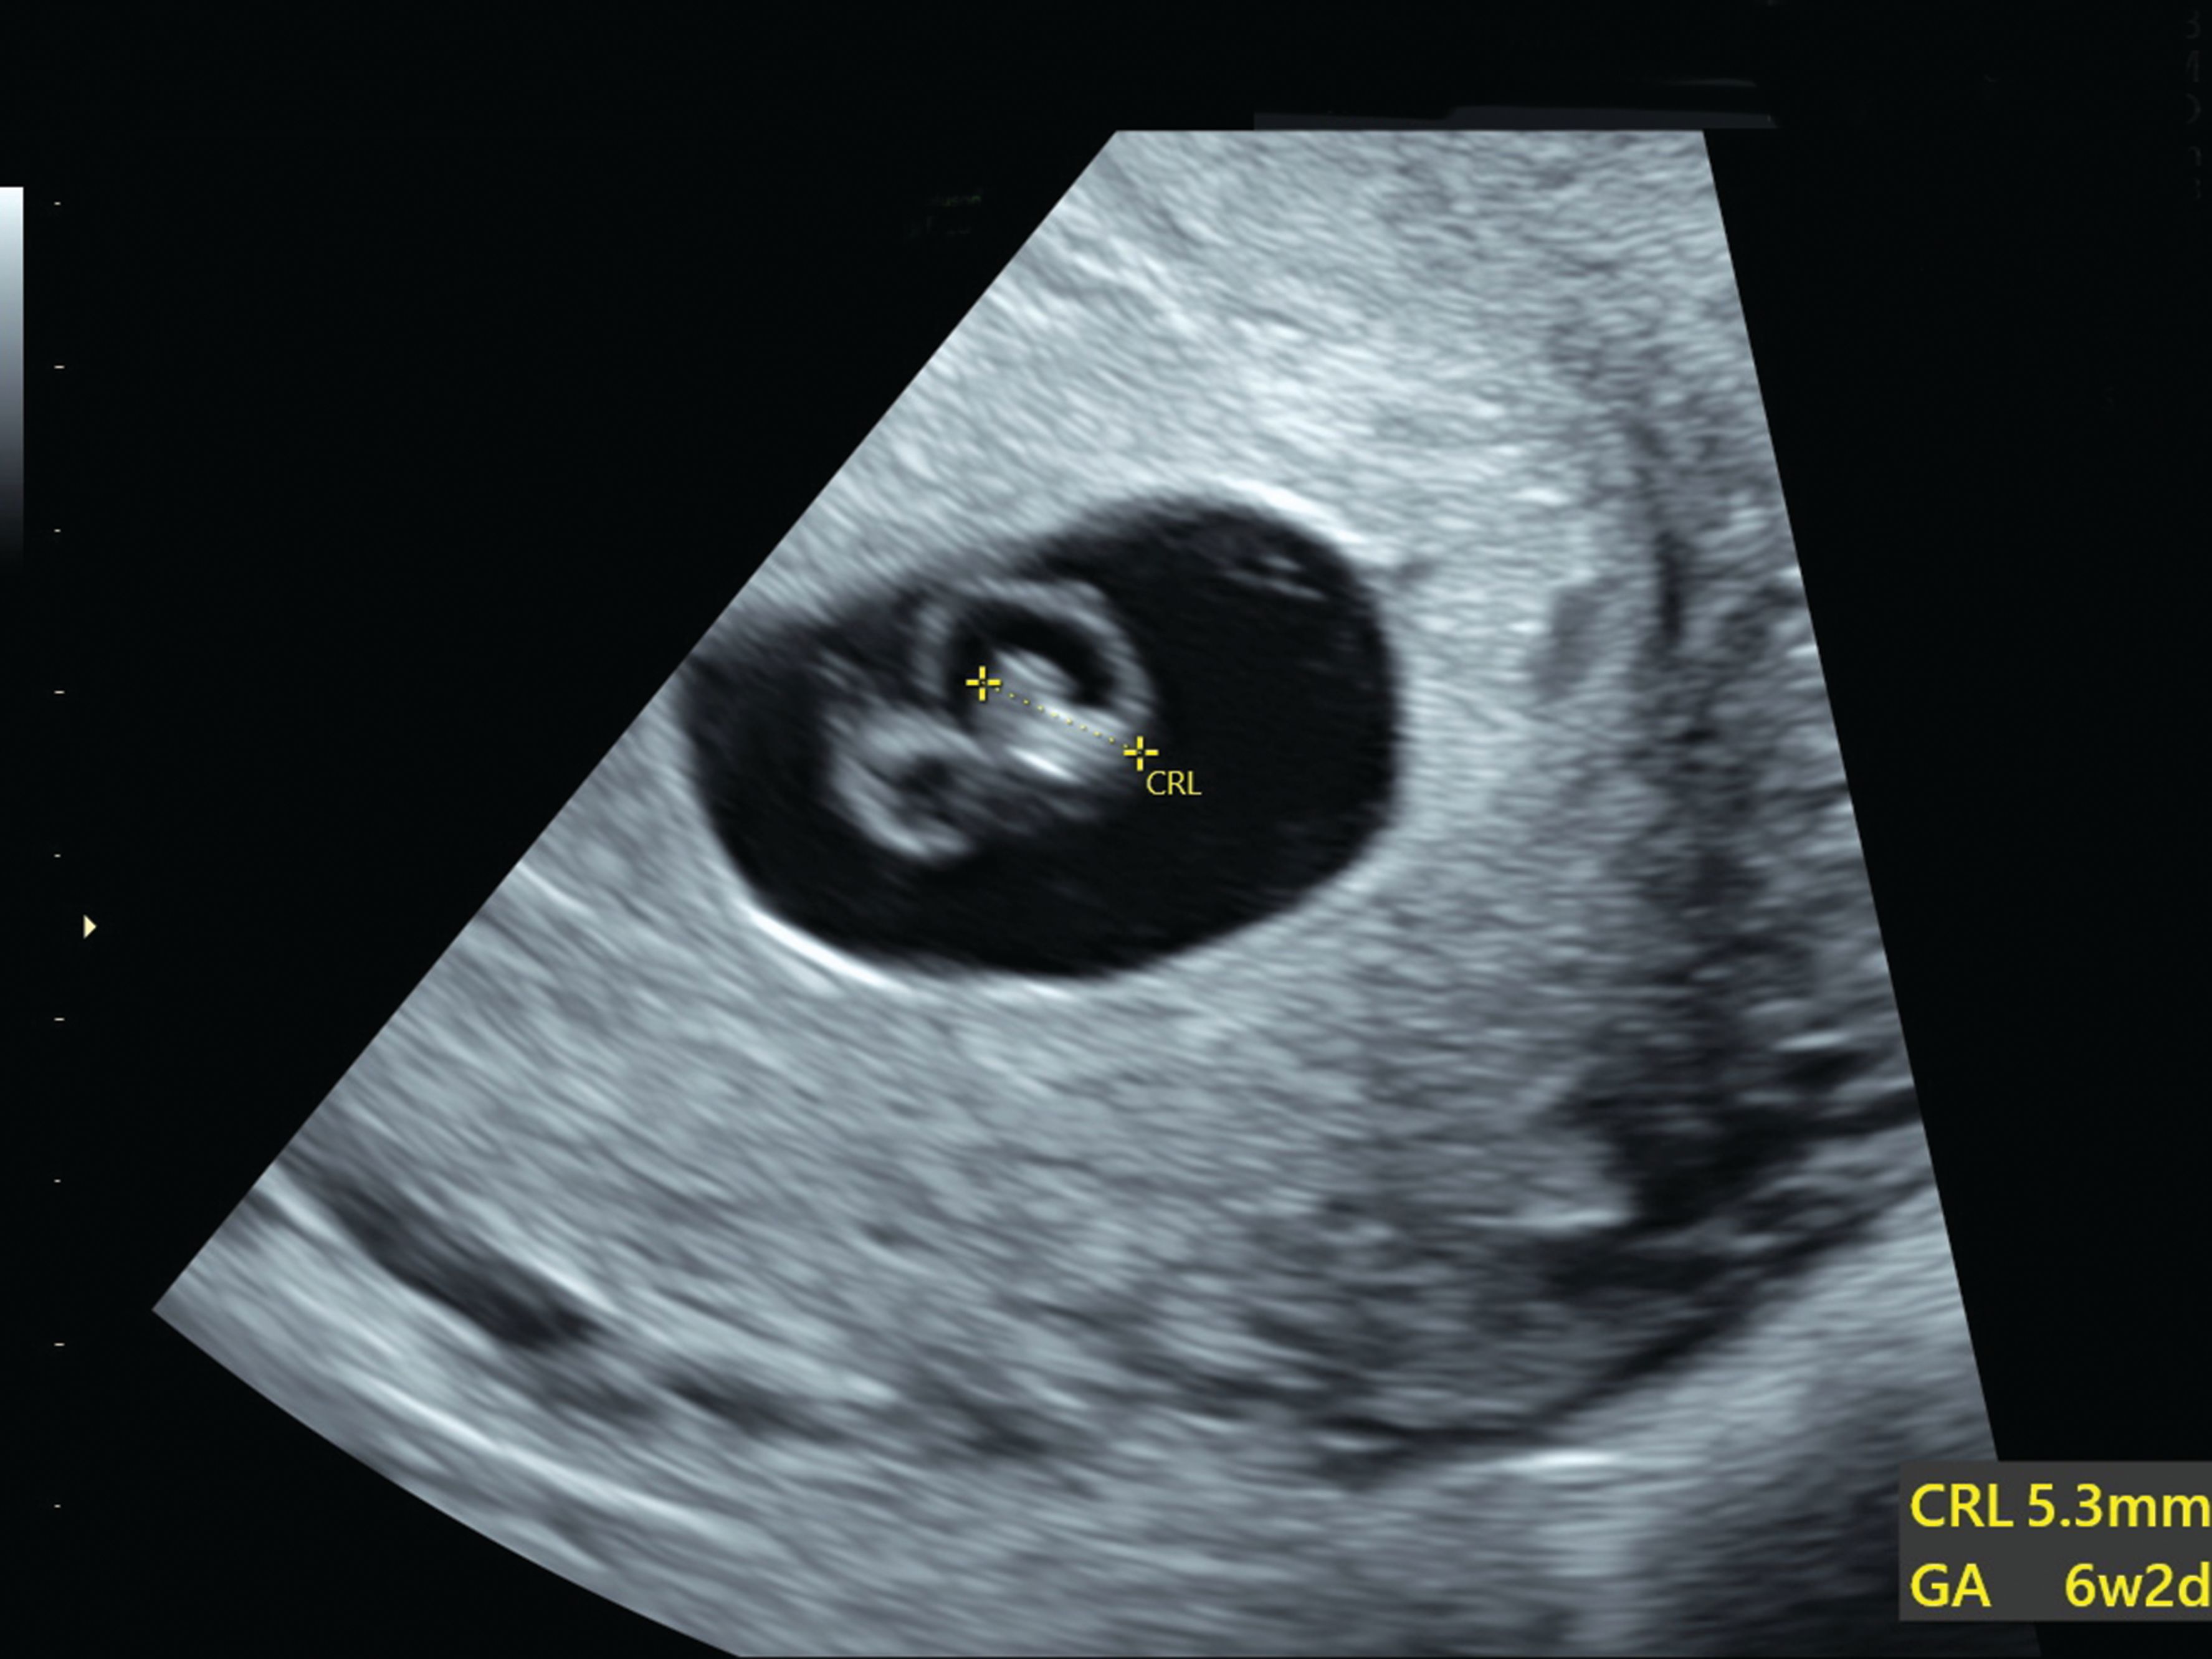

It is too soon to see the baby on the scan. Incorrect timing is one of the most common causes of an inability to see a gestational sac on an early ultrasound especially in the absence of. Can a baby hide in an.

I went and had blood drawn my. It is possible to be pregnant and see nothing on an ultrasound. Earlier than this and there will be a visible sack but you wont necessarily see a baby.

Web Incorrect timing is one of the most common causes of an inability to see a gestational sac on an early. Though it is rare it is possible to have a hidden twin that is not visible during early ultrasound screenings. There are a few possibilities as to why the gestational sac doesnt show up during a 5-week ultrasound.

6 Week 1 Day Ultrasound 13mm Sac No Fetal Pole No Yolk Sac Could It Be Ok